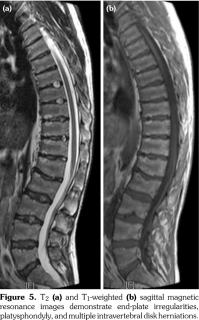

Physical examination revealed decreased range of motion in shoulders, wrists, metacarpophalangeal, proximal IP, distal IP, and ankle joints. In particular, the IP, metacarpophalangeal and metatarsophalangeal joints had bony enlargements, mild tenderness and flexion contractures; however, no signs of inflammation like redness, effusion, or other signs of synovitis (Figure1). The patient also had mild spinal scoliosis, significant thoracolumbar kyphosis, and pectus excavatum deformity. Furthermore, he had saddle nose deformity, bilateral floppy pinna and audiovestibular dysfunction (sensorineural hearing loss and tinnitus) (Figure 2). The rest of the systemic examination was unremarkable.

Radiographs of the hands showed enlargement of metaphyses, flattening of epiphyses, and narrowing of joint spaces with no erosions. Lateral radiograph of the foot revealed bilateral large ossified trigonum attached to the talus (mega os trigonum) (Figure 3). Radiographs of the spine showed increased kyphosis, generalized platyspondyly particularly at the thoracolumbar junction, and irregularity of the vertebral end- plates (Figure 4). Magnetic resonance imaging of thoracolumbar spine demonstrated irregularity in vertebral end-plates, multiple disk herniations, and platyspondyly (Figure 5). Dynamic contrast- enhanced magnetic resonance imaging of the wrist did not reveal any signs of synovial inflammation.

Clinical features of PPD have been described in several reports.(9-11) The radiographic features include varying degrees of epiphyseal involvement with enlargement of the epi-metaphyseal region, progressive joint narrowing, generalized platyspondyly, multiple intervertebral herniations, kyphoscoliosis, mega os trigonum and bone destruction with aging.(2,6,10) Our patient had progressive restriction of several joints, IP enlargements, dysplastic bone/cartilage changes, mega os trigonum and platyspondyly, with normal acute phase reactants. The presence of dysmorphic features and the absence of inflammatory signs should alert the physicians for the possible hereditary dysplasias like PPD.

Articular manifestations may occur in 70% to 80% of patients with RP. The most frequent pattern is migratory, seronegative, episodic, and asymmetric inflammatory oligo/polyarthritis. Articular lesions are generally non-erosive/non- destructive, unless the presence of underlying RA. Arthritis associated with RP may affect all synovial joints; however, metacarpophalangeal, IP and knee are the most commonly affected joints. Plain radiographs typically illustrate mild joint space narrowing and juxtaarticular osteoporosis. In patients with RP, cartilage damage may also lead to pectus excavatum deformity.(15) Despite occurrence of seronegative, non-erosive, non- inflammatory polyarthritis, RP does not cause abnormalities in vertebrae, dysplastic bony changes, and progressive arthropathy. However, presences of chronic polyarthritis and progressive loss of joint motions with enlargement of the metacarpal and phalangeal epiphyses, mega os trigonum and spinal abnormalities including platyspondyly make our case an exceptional and interesting one.